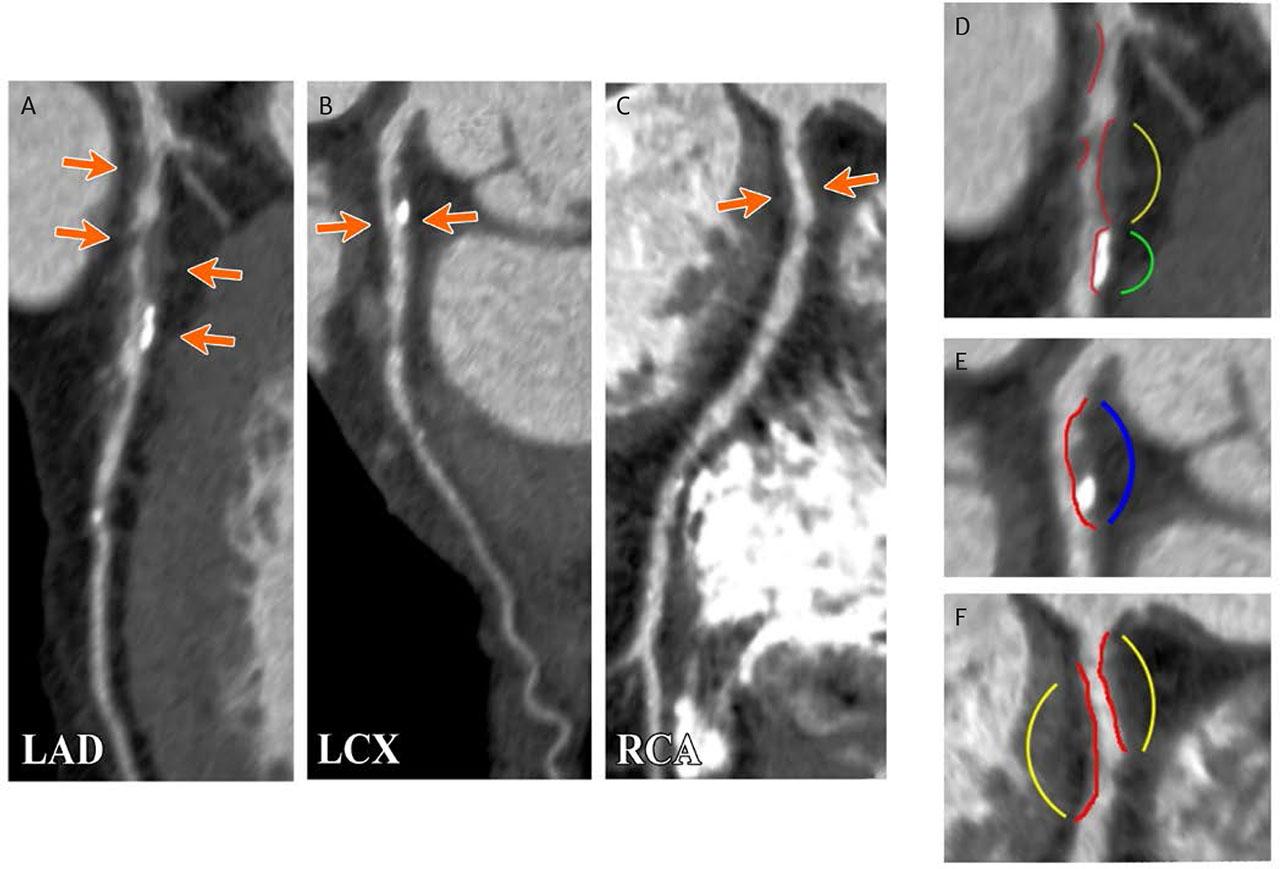

FIGURE 1.